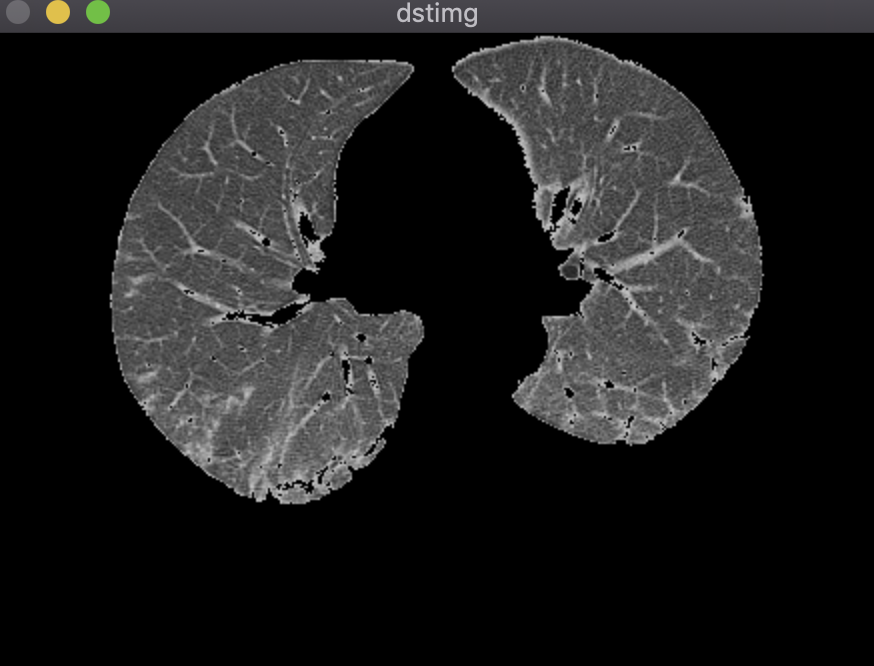

结果:

鼠标先在二值图左肺选取一个种子点,按‘b‘进行分割;然后在二值图右肺选取一个种子点,按‘b‘进行分割,之后做或运算,将两个分割结果合并;最后与灰度图做与运算得到最终分割结果。

区域生长算法有几个缺点:

1.需要人工选取种子点,不能实现全自动化;

2.二值化时需要设置阈值,阈值参数影响较大;

3.后期还得做平滑运算;

4.需要设置领域像素与种子点灰度值差的阈值。